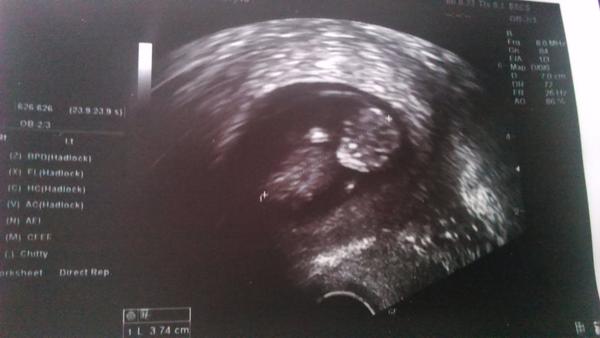

@miska_hryzka velmi pekna foto.Aj my mame take 😊 Gratulujem.

@laska07 ďakujem 🙂 pekne sa otočilo alebo lekár inak otočil ultrazvuk 🙂 v piatok bolo inak 🙂 aj tebe veľa zdravicka hlavne 🙂

@miska_hryzka no krásne rastiete

@miska_hryzka predpokladám ze si uz cez niečo 10 tyzden Hm?

@gabikamicka chystáš sa az domov k lekárovi? Áno 11.týždeň presne 10tt+3 🙂